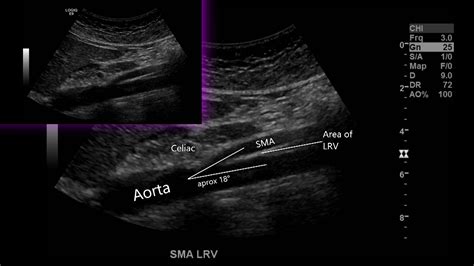

To grasp why this syndrome causes such intense discomfort, it helps to visualize the anatomy. Under normal circumstances, blood flows freely from the kidney back to the heart. In Nutcracker Syndrome, the angle between the aorta and the mesenteric artery becomes too narrow, effectively "pinching" the left renal vein. This leads to increased venous pressure, which can cause the vein to swell and potentially lead to the formation of collateral veins as the body desperately tries to redirect blood flow.

Doppler Ultrasound Measures the velocity of blood flow to detect narrowing in the renal vein.